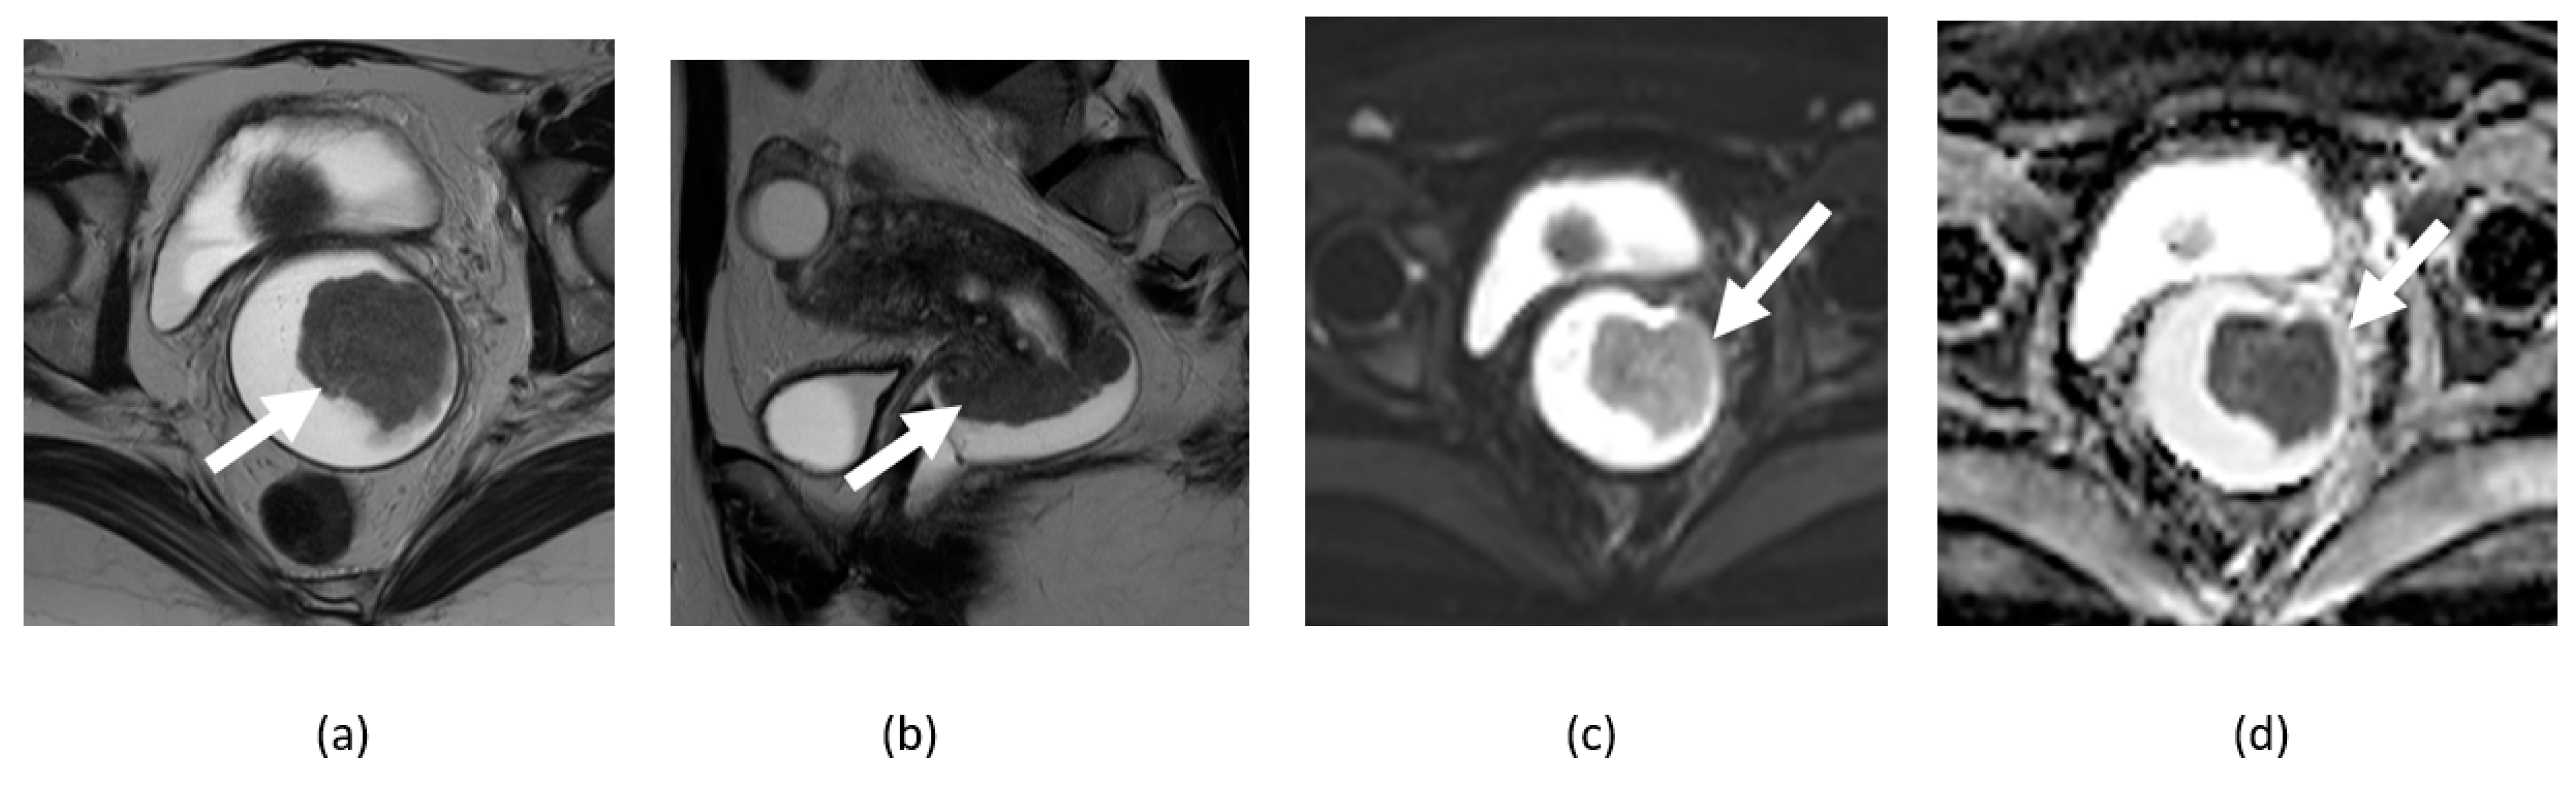

3.6. Ovarian Fibroma, Fibrothecoma, and Thecoma